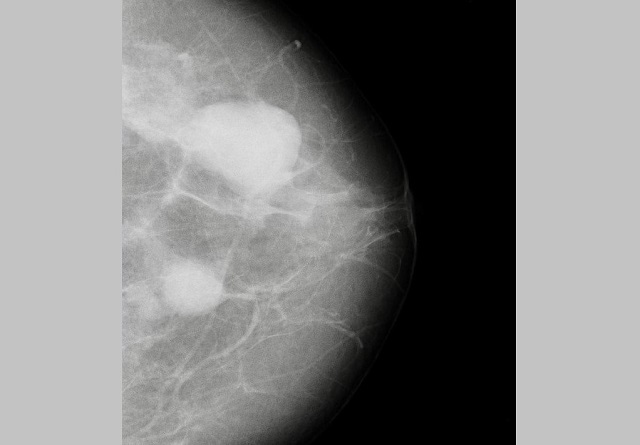

В Набережных Челнах у пациентки обнаружили два объемных образования молочной железы во время промышленной диспансеризации. Об этом сообщили в телеграм-канале «Горздрав Челны».

Женщине чуть больше 40 лет. Она пришла на диспансеризацию в поликлинику по направлению от работодателя. На маммографии врачи обнаружили образования. Сейчас пациентка наблюдается у врача-онколога.

Фото: телеграм-канал «Горздрав Челны»